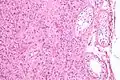

Intermediate magnification micrograph of a Leydig cell tumour, H&E stain